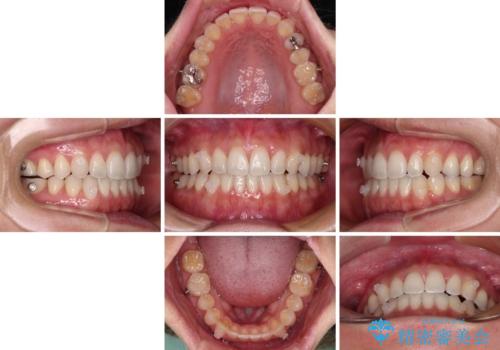

【モニター】狭い上顎歯列とオープンバイト 急速拡大装置を用いた矯正治療

- 前歯の開咬を気にして来院された患者様です。

上顎歯列が狭窄していたため、急速拡大装置により上顎骨を側方に拡大し、その後インビザラインにて矯正治療を行うこととしました。

舌の突出癖が開咬の原因であったので、改善のための舌トレーニングを行っていただきました。

舌トレーニングは後戻りにも大きく影響するため、とても重要なトレーニングです。